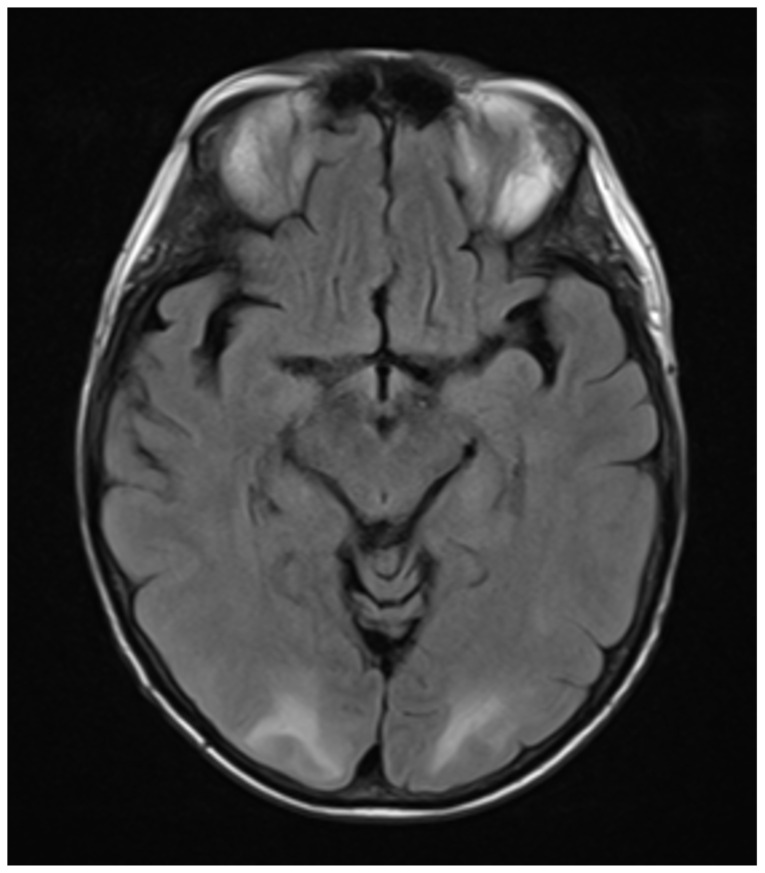

Introduction: Posterior reversible encephalopathy syndrome (PRES) is an illness in which a person can present with acutely altered mentation, drowsiness or sometimes stupor, visual impairment, seizures (focal or general tonic-clonic), and sudden or constant, non-localized headaches.1 Patients at risk for developing PRES include those with underlying hypertension, preeclampsia, kidney disease, liver disease, exposure to cytotoxic medications or immunosuppressants, autoimmune disorders or sepsis. As a syndrome, PRES has gone underdiagnosed given its broad symptomatology. While it appears to affect people of all ages, it is more commonly found in middle-aged females. The underlying cause for PRES remains unclear, but some proposed mechanisms center on the dysregulation of cerebral autoregulation, the brain's ability to maintain constant cerebral blood flow over a range of blood pressures via the constriction or dilation of the cerebral blood vessels.2 The treatment for PRES includes management of hypertension as well as diagnosing and treating the underlying etiology. This disease process needs to be recognized early by the emergency provider to reduce mortality.Eclampsia and other hypertensive disorders in women affect as many as 10% of all pregnancies worldwide and are responsible for approximately 10% of all maternal deaths in the United States.3 Eclampsia is defined as new onset seizures in a woman with a history of preeclampsia who is between 20 weeks gestation and within four weeks postpartum.4 As an emergency medicine provider, it is imperative to be able to manage and treat a patient with eclampsia to decrease mortality and morbidity of the mother and fetus. Management of eclampsia includes treatment for seizures using magnesium sulfate, treatment for hypertension, and emergent obstetrics consult for possible delivery of the fetus.4.

Educational objectives: At the end of this oral boards session, examinees will be able to: 1) demonstrate familiarity with the structured interview oral board format and case play; 2) recognize the history and exam features concerning for PRES and eclampsia; 3) order appropriate diagnostic workup for postpartum and hypertensive emergencies including eclampsia and PRES; 4) understand treatment options for the management of eclampsia (intravenous [IV] magnesium sulfate, IV antihypertensive therapy, and emergent consultation with an obstetrician [OB/GYN]); 5) understand threshold for taking control of airway in patients with eclampsia; 6) understand indications for ordering brain imaging in patients with eclampsia and altered mental status; and 7) demonstrate effective communication with treatment team/family members as well as correct disposition of the patient to a higher level of care (intensive care unit [ICU]).